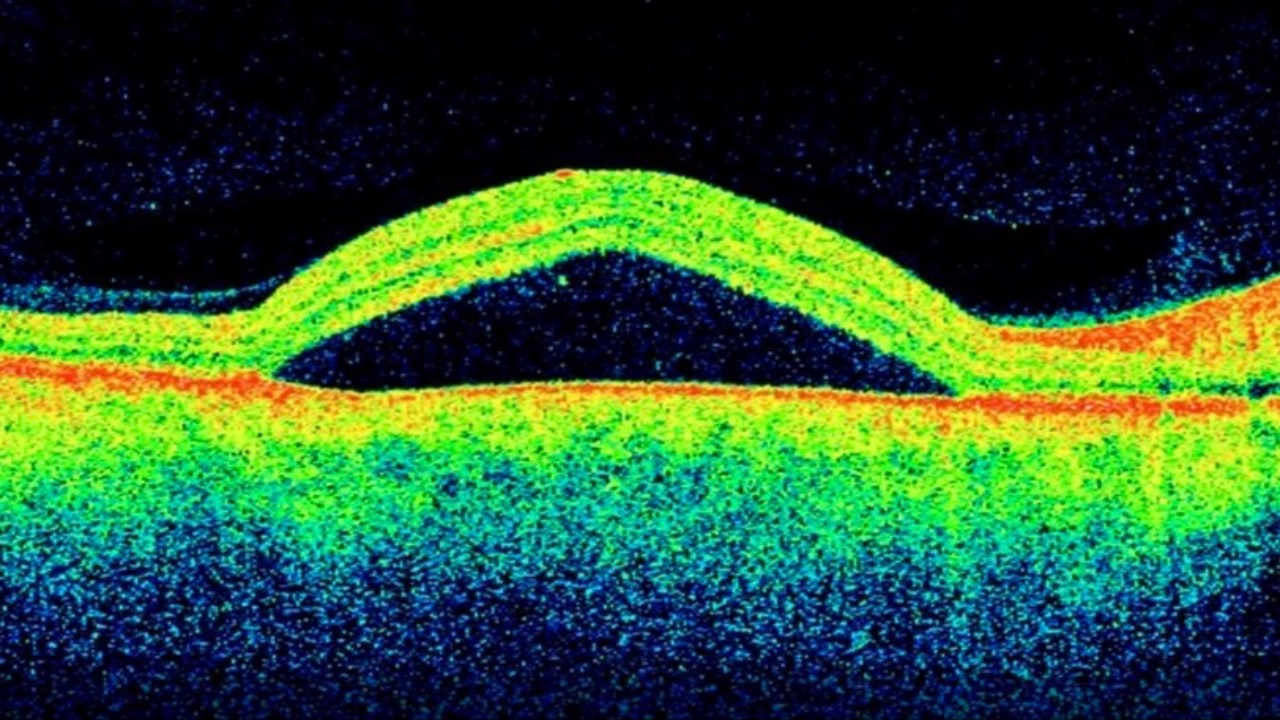

Central Serous Chorioretinopathy Redux

Sometimes personality really doesn't matter...

Central Serous Chorioretinopathy (CSC) has long been associated with younger stressed-out males & Type A personalities - likely due to higher circulating cortisol levels being released via the adrenals. Exogenous corticosteroid use has also been a m...